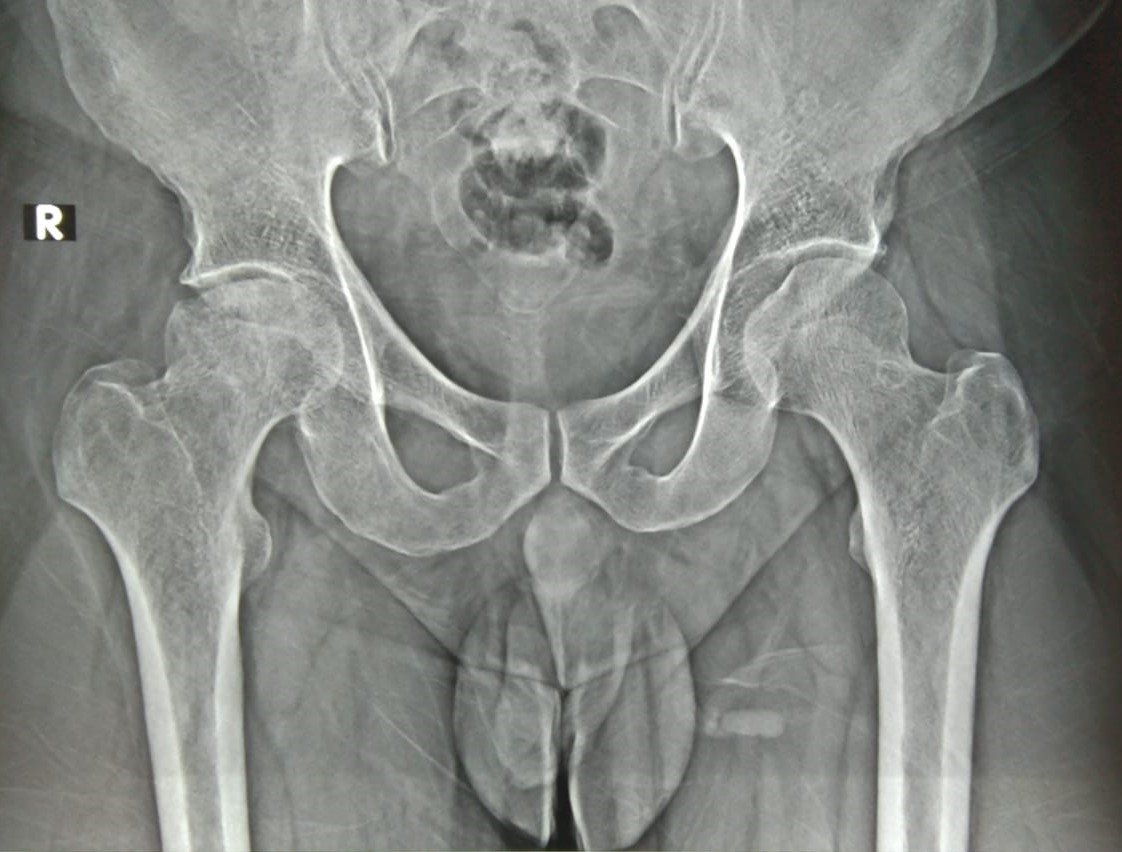

Pre-Op X-Ray